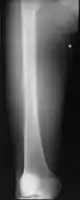

Medical imaging usually shows a well-defined wide-based bony growth on the surface of bone.[5] It can be pedunculated and irregular, giving it a "bizarre" appearance, and is not connected to underlying bone.[2]

MRI mid-upper arm

MRI mid-arm axial view

X-ray hand, BPOP 2nd metacarpal

X-ray hand, BPOP 2nd metacarpal (side view)